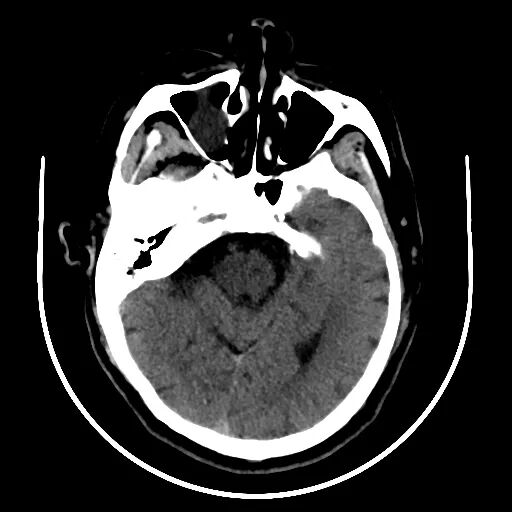

查体BP 160/89mmHg,清醒,双眼左侧凝视位、不可纠正,混合性失语,右侧中枢性面舌瘫,右侧肢体肌力0级,右侧病理征阳性。NIHSS评分18分。随机血糖4.8mmol/L。心电图:正常。颅脑CT无出血及新发梗死灶,多模态CT示左侧大脑中动脉闭塞、左侧大脑半球低灌注。

颅脑CT无出血及新发梗死灶。